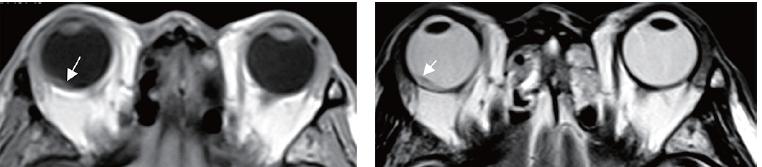

可是在浩瀚的各类CT、MRI学术专著中,介绍我们小眼科的部分永远都是那么一点点,看了半天“砖头书”,实操起来还是没底气。

《眼科CT与MRI学习精要》在身,让行走在江湖的各位小伙伴们不再提心吊胆。

这是我们出品的第6个分册,也是眼科CT与MRI的第2版。